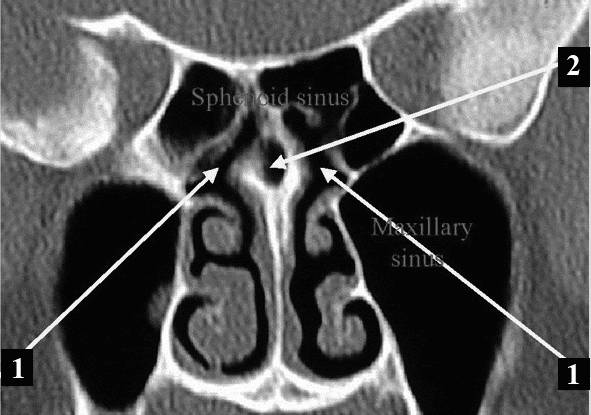

| Диагностика | Осмотр ЛОР-врача, риноскопия, эндоскопия носа, рентгенография придаточных пазух носа, КТ придаточных пазух носа (наиболее информативно), лабораторные анализы крови. | Не является частью лечения, но необходима для его назначения. |

На сегодняшний день наиболее надежным способом диагностики данного заболевания является магнитно-резонансная томография. Этот метод подходит даже для детей, так как не использует ионизирующее излучение и позволяет выявить воспалительные процессы в околоносовых синусах и патологии решетчатой кости.

Для диагностики у взрослых также применяются рентгенография, риноскопия и эндоскопическое исследование глубоких носовых пазух.